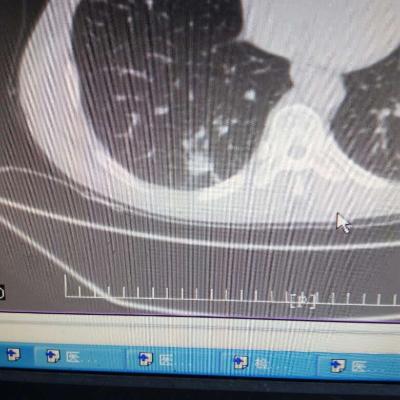

主诉:反酸、烧心5年,加重1年。 病史:患者5年前饮酒出现反酸烧心,并嗳气症状,剑突下烧灼感,饮酒及平卧后加重,无恶心呕吐,无腹痛腹泻,无吞咽困难,服用“达喜”后症状可缓解,易反复发作。3天前我科门诊示:胃镜反流性食管炎(LA-B),现为进一步诊治入院。

1.胃食管反流病 1.1反流性食管炎LA-B 2.食管裂孔疝 处理:患者诊断明确,行腹腔镜下食管裂孔疝修补术+胃底折叠术。

患者术后一周出院,反酸、烧心、嗳气症状明显缓解,无吞咽不畅等症状。 讨论:对于诊断有食管裂孔疝病人的胃食管反流病,且用药有一定疗效,建议行手术治疗,行腹腔镜下食管裂孔疝修补术,修补了膈裂孔,同时行胃底折叠术,加紧了贲门括约肌压力,共同形成抗“反流瓣”。